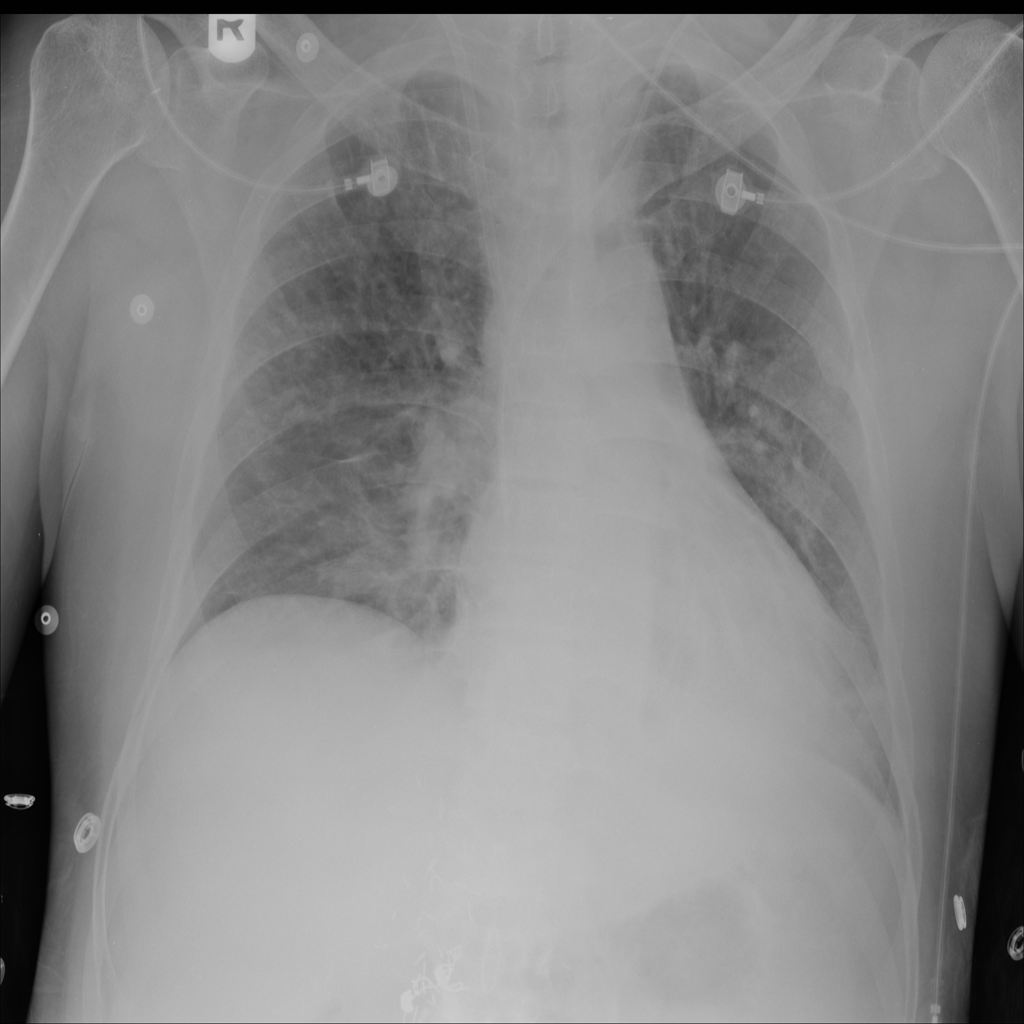

PAT-A1E2 · IMG-001Pneumonia

PAT-A1E2 · IMG-001

AP